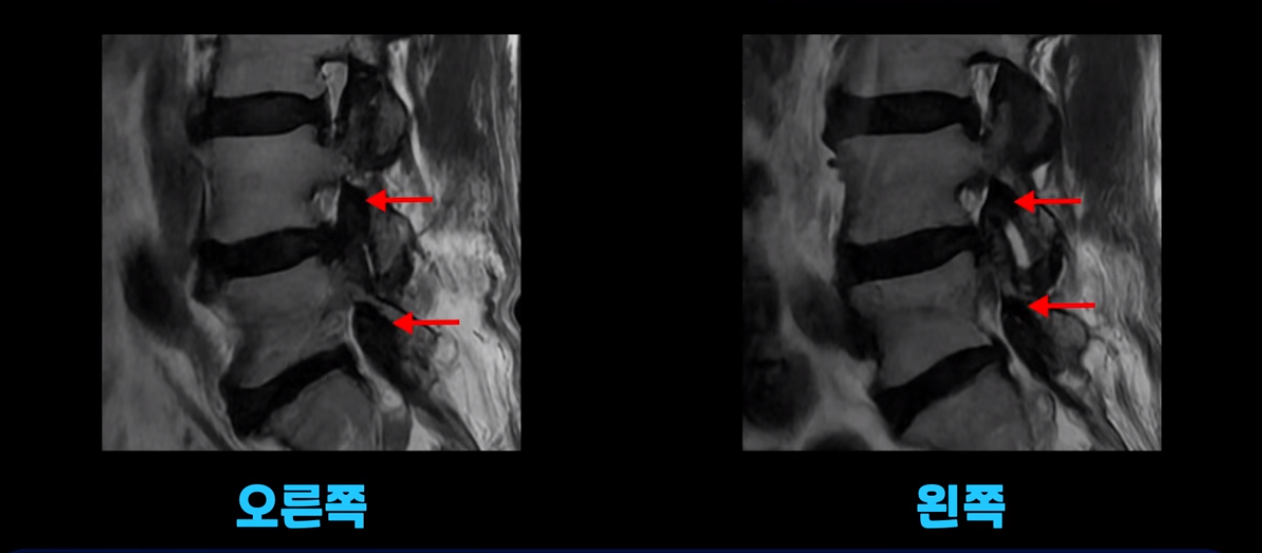

MRI를 보면서 설명해 드리겠습니다. 2마디에 퇴행성디스크가 있는데 심하지는 않습니다.

4번 5번에 척추관 협착이 있는데 신경을 심하게 누를 정도로 심하지는 않습니다.

오른쪽 왼쪽 신경 가지가 나가는 추간공도 좁아져는 있지만 아주 심하지는 않습니다.

이 환자분의 가장 큰 문제는 허리를 펴는 근육인 척추기립근이 상당 부분 지방으로 변해서 하얗게 보이고 기립근의 크기도 많이 작아져 있습니다.

이 기립근은 허리를 펴주는 근육인데 이렇게 문제가 생기면 허리가 구부러집니다. 또한 이분의 근육 상태를 알 수 있는 근감소증 검사에서 중증 근감소증 진단이 나왔습니다.

평균적인 동년배들에 비해 근육량이 많이 줄어든 겁니다. 이렇게 근육량도 많이 줄어들고 또 남아있는 근육이 지방으로 변한 상태에서 그나마 남아있는 근육들마저도 뭉치고 굳어서 제 기능을 못 하면 허리가 구부러지고 걸을 때 다리가 힘들고 아플 수밖에 없습니다. 그런데 근육 치료와 이런 근육의 문제를 MRI를 찍어보고 협착이 조금이라도 보이면 협착증으로 진단하고 주사 놓고 안 되면 수술까지 하는 경우들이 있습니다.